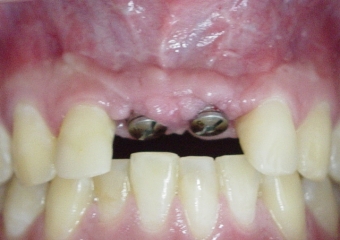

Dois implantes instalados, com cicatrizadores